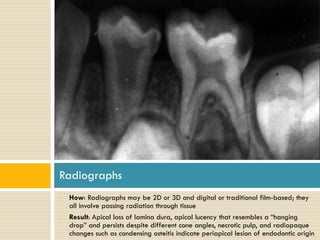

Radiographs

•

How: Radiographs may be 2D or 3D and digital or traditional film-based; they

all involve passing radiation through tissue

Result: Apical loss of lamina dura, apical lucency that resembles a “hanging

drop” and persists despite different cone angles, necrotic pulp, and radiopaque

changes such as condensing osteitis indicate periapical lesion of endodontic origin